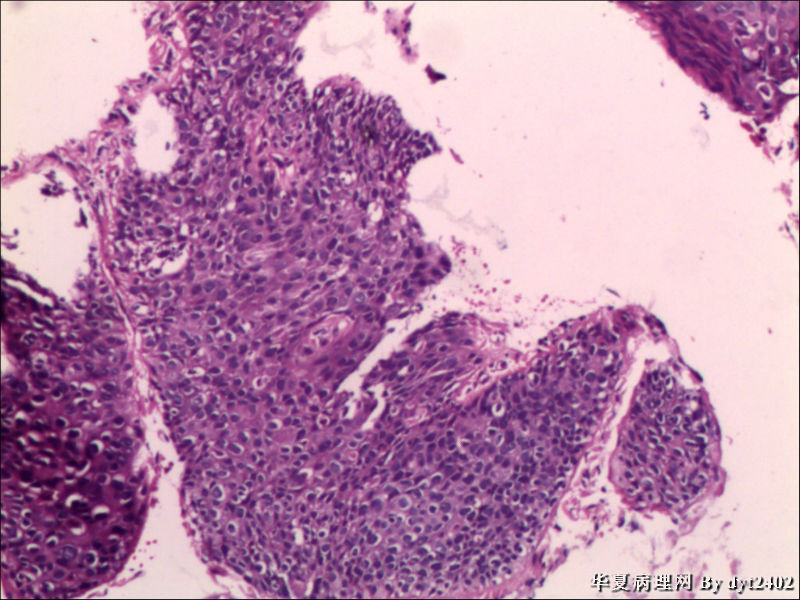

这样的外阴病变 发个原位癌是否合适?

• 这样的外阴病变 发个原位癌是否合适?图2

图2

VIN III,做个银染或者标个免疫组化看一下基底膜是否完整。

原位癌够了,不排除其他地方有浸润。

似乎有浸润了

VIN III

看上去好像还完整 只是经常看见图5 那样结构的就觉得可能还有更重病变